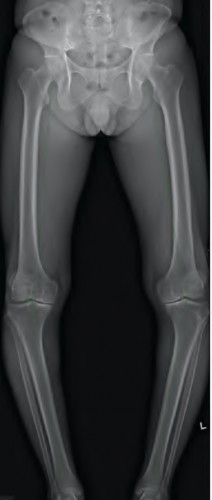

A 45-year-old female with developmental dysplasia of the hip (DDH) presents for THA. Preoperative radiographs show the femoral head is subluxated, with 80% proximal migration relative to the height of the normal true acetabulum. Based on the Crowe classification, what type of dysplasia does she have?

Explanation